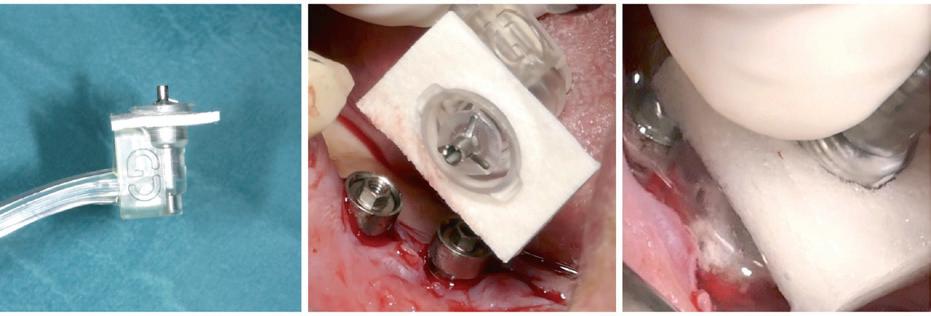

Eine mögliche Lösung könnte das 2021 eingeführte Reinigungssystem GalvoSurge® bieten. Bei diesem Verfahren werden Zahnimplantate elektrochemisch dekontaminiert, indem das Implantat mit einer speziellen Reinigungsflüssigkeit besprüht und eine elektrische Kleinstspannung angelegt wird.

Als Folge fließt zwischen dem Sprühkopf (Anode) und dem Implantat (Kathode) Strom und das Wasser in der Elektrolytflüssigkeit (Hydroxy Carbonsäure, Natriumsalz, destilliertes Wasser) wird in Wasserstoff Kationen (H+) und Hydroxid Anionen (OH-) aufgespalten. Die dadurch entstandenen Wasserstoffbläschen sollen den Biofilm aufbrechen und ihn von der Implantatoberfläche ablösen (Abb. 1c).(4, 5) Dieses Verfahren dauert ca. 2 Minuten pro Implantat und ist mit den meisten Implantatsystemen kompatibel.

Aufgrund des jetzigen Sprühkopfdesigns beschränkt sich die Anwendung von GalvoSurge® jedoch auf verschraubte Suprakonstruktionen. Diese müssen vor der elektrolytischen Dekontamination abgenommen werden, damit eine sichere Verbindung zwischen dem GalvoSurge® Sprühkopf und der Implantatinnenverbindung hergestellt werden kann (Abb. 1a,b).

Abbildung 1. Der Sprühkopf (a) wird intraoperativ nach Abnahme der Suprakonstruktion (b) aufgesetzt und die während des Reinigungsprozesses entstehenden Wasserstoffbläschen sollen den Biofilm aufbrechen (c). Fotos © Kristina Bertl

Nach dem Abschrauben der Restauration muss ein Lappen abgehoben werden, um das periimplantäre Entzündungsgewebe gründlich entfernen zu können, da die reinigende Wirkung von GalvoSurge® sich nur da entfalten kann, wo die Spüllösung Kontakt zur Implantatoberfläche hat.